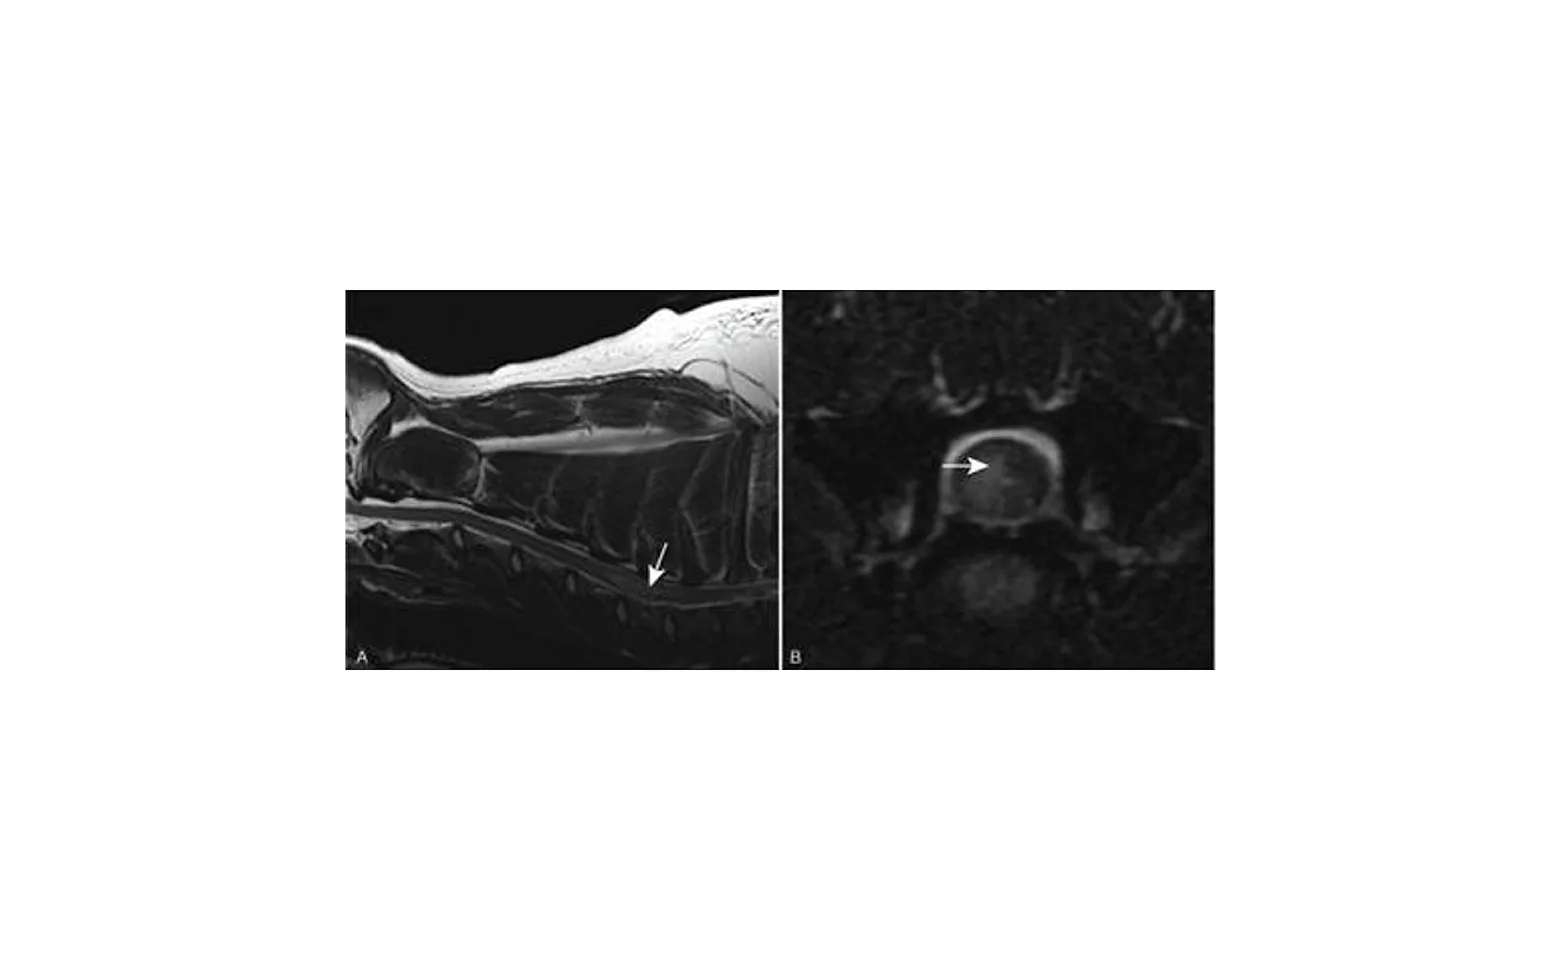

The first step in diagnosing this disease is to rule out other possible conditions that could cause similar neurologic signs. This may include intervertebral disk disease, trauma, cancer, infectious agents, or inflammatory conditions. Usually advanced imaging (CT, myelogram, or MRI) is necessary to help diagnose FCE. CT scan and myelogram may show a region of spinal cord swelling or a focal area of abnormal appearance. MRI may be able to locate the area of the spinal cord affected by a focal region of abnormal intensity. Below are MRI images showing a hyperintense region consistent with FCE.